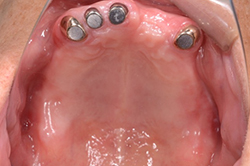

マグネット義歯(金属床)

磁石の力で義歯をくっつけるので、見た目がわからなくなるだけでなく、外れにくく、噛みやすい、異物感の少ない(義歯を小さくできるため)入れ歯にできます。(実際は入れ歯だとわかりません)

「前の医院ではただ歯を抜かないようにと掃除だけしてもらってたが、どんどん歯周病は悪くなり全く噛めない。」と来院されました。

残せる歯は本格的に歯周病治療しマグネットを被せます。

義歯と言っても金具もなく全く外れないので、綺麗で快適に噛めるようになりました。

下顎は残せる歯が少なかったため奥歯部位にインプラント維持装置も追加 |